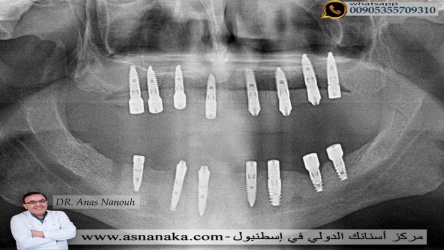

صوره شعاعيه لزراعات الاسنان وقت تم زراعه ثمانيه زراعه في الفك العلوي وسبع زراعات في السفلي